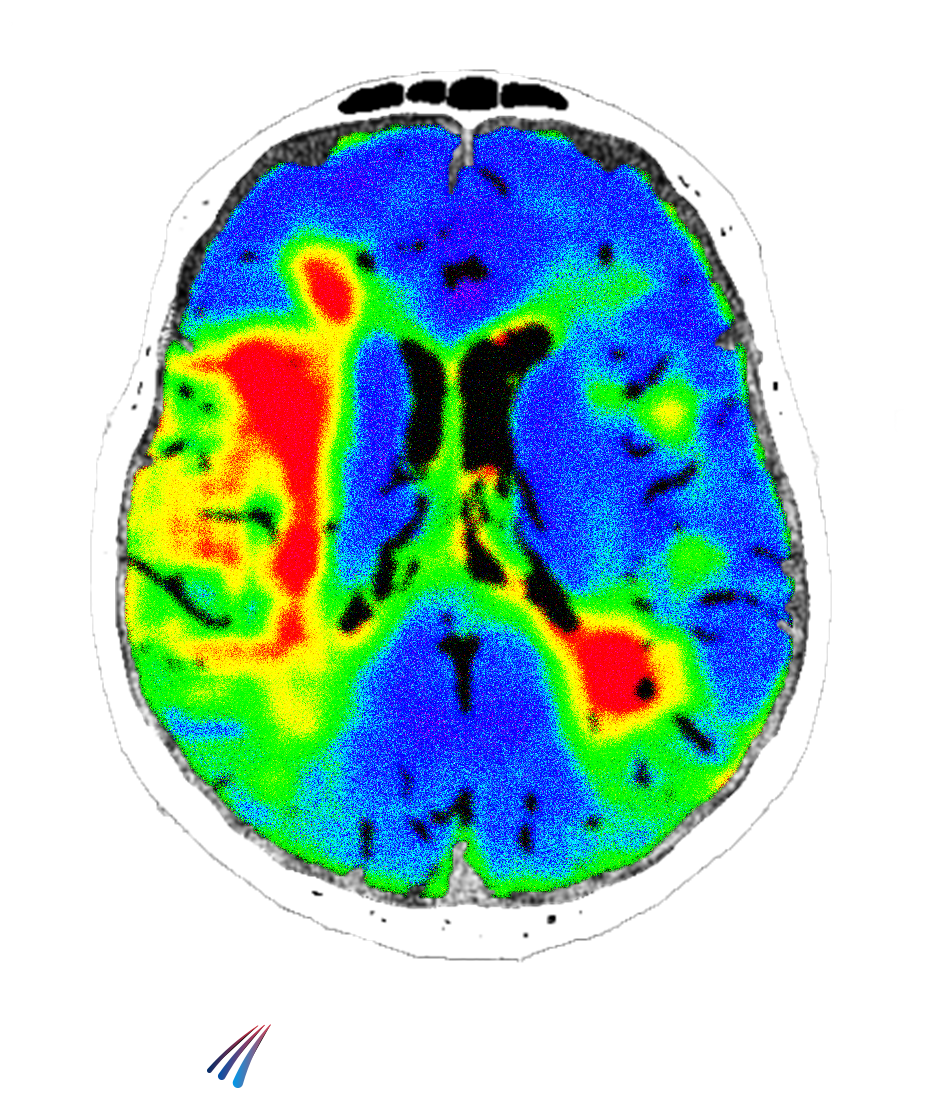

Virtual CT Perfusion

Our technology leverages advanced deep learning to generate perfusion maps directly from non-contrast CT scans. By eliminating the need for traditional perfusion CT, we enable faster, simpler, and more accessible stroke triage. Clinicians gain rapid insight into brain blood flow and tissue viability—helping them make critical treatment decisions when every minute counts.